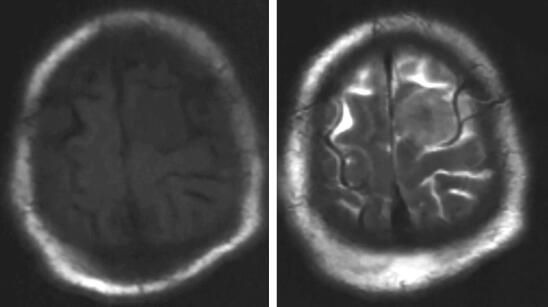

患者,男性,80岁,因“发现左额占位5年,进行性失语1月余”入院。患者于5年前体检时发现左额占位(图1),T1等信号T2等信号,未进一步行增强检查。患者外院就诊考虑患者脑膜瘤可能大,结合患者年龄建议保守治疗密切随访。患者之后未定期就诊复查头颅MRI。患者自1个月前开始出现言语迟缓,主要表现为言语表达困难,无言语理解障碍,进行性加重,伴右侧肢体肌力进行性减退,左侧肢体肌力未受影响。患者就诊外院后进一步查头颅MRI提示左额多发病灶,浅部病灶明显均匀强化,考虑患者既往病史考虑脑膜瘤可能大;深部病灶不均匀强化,伴坏死,高级别胶质瘤不能除外(图2)。患者进一步查头颅FDG-PET提示左额浅部病灶放射性摄取值轻度增高,SUV值最大8.9,结合病史,考虑颅内原发低代谢肿瘤(脑膜瘤可能大);左额深部侧脑室上方病灶放射性摄取异常增高,SUV最大值21.6,考虑脑内原发恶性肿瘤可能大,体部PET显像未见FDG代谢明显异常增高(图27-3)。患者入院后积极完善相关检查,排除手术禁忌后行左额浅部病灶切除+深部病灶活检术,术中冷冻结果提示左额浅部病灶为脑膜瘤,深部病灶为小圆细胞恶性肿瘤。

图1 患者2012年头颅MRI平扫提示左额病灶,T1等信号(左),T2等信号(右),未行增强扫描